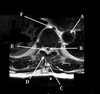

Q

What is letter A?

A

CSF

11

What is letter B?

SPINAL CORD

12

What is letter C?

LAMINA

13

What is letter D?

DORSAL NERVE ROOT

14

What is letter E?

VENTRAL NERVE ROOT

15

What is letter F?

VERTEBRAL BODY

16

What is letter G?

SPINOUS PROCESS

17

What is letter H?

TRANSVERSE PROCESS

18

What is letter J?

VERTEBRAL ARTERY